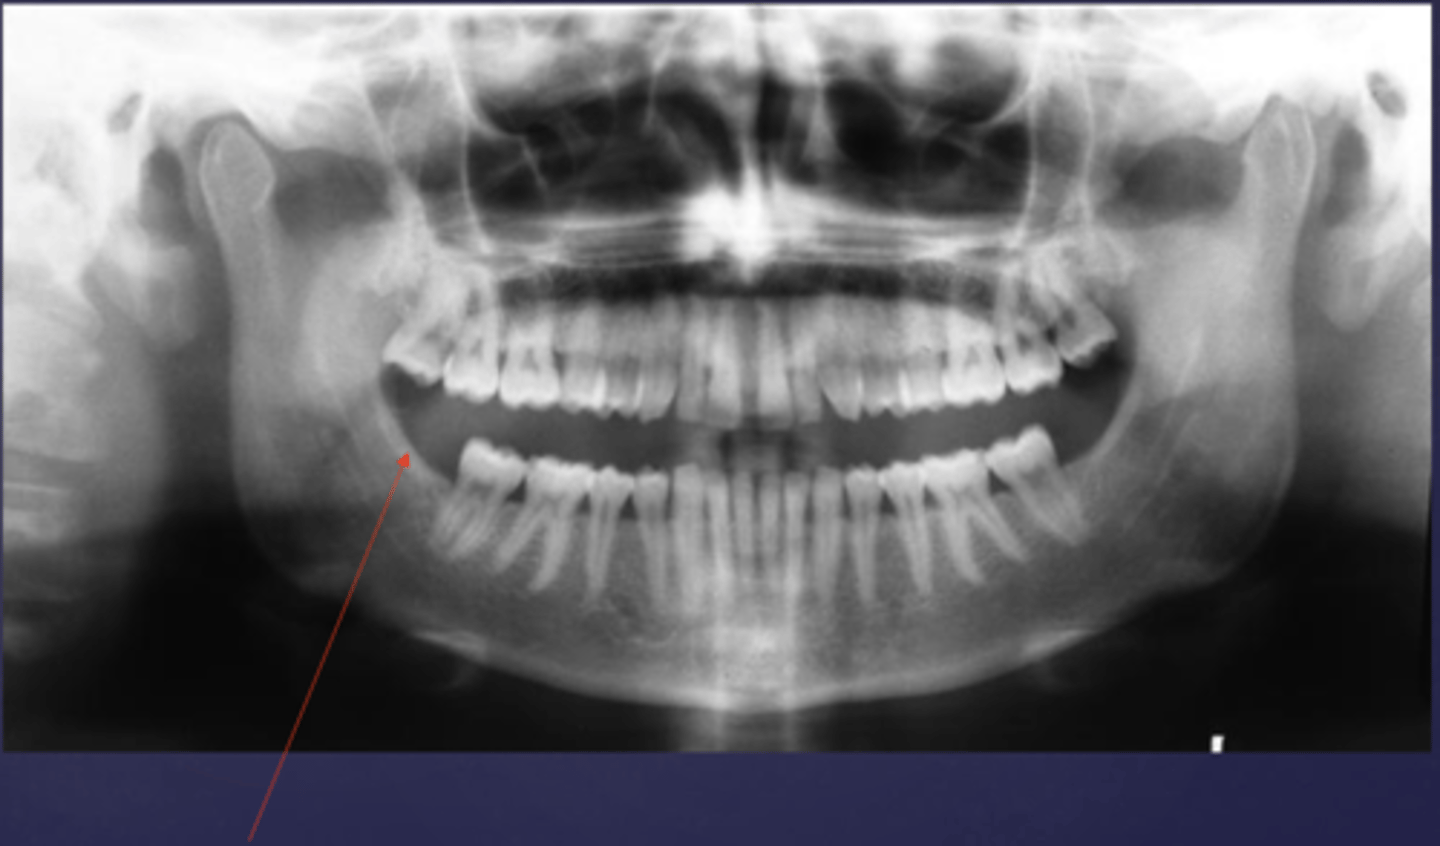

in order to prevent the cervical vertebrae from appearing on a pano, you can make sure that the patient's chin is tilted slightly _____

downward

the blue arrow is pointing to what type of image of the cervical vertebrae?

ghost image